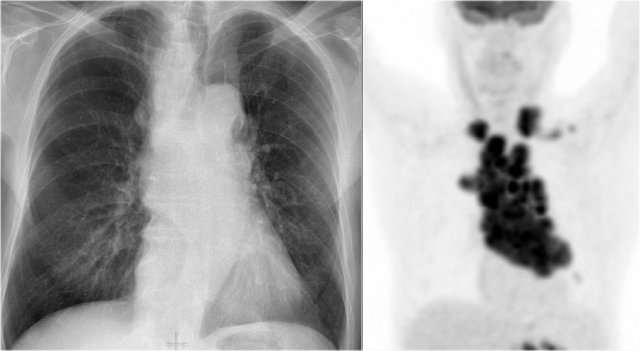

Another common cause of displacement of the azygoesophageal line is subcarinal lymphadenopathy.

Notice the displacement of the upper part of the azygoesophageal line on the chest x-ray in the area below the carina.

This is the result of massive lymphadenopathy in the subcarinal region (station 7).

There are also nodes on the right of the trachea displacing the right paratracheal line.

On the PET we can appreciate the massive lymphadenopathy far better than on the CXR.

There are also lymphomas in the neck.

this is an important finding, since these nodes are accessible for biopsy.